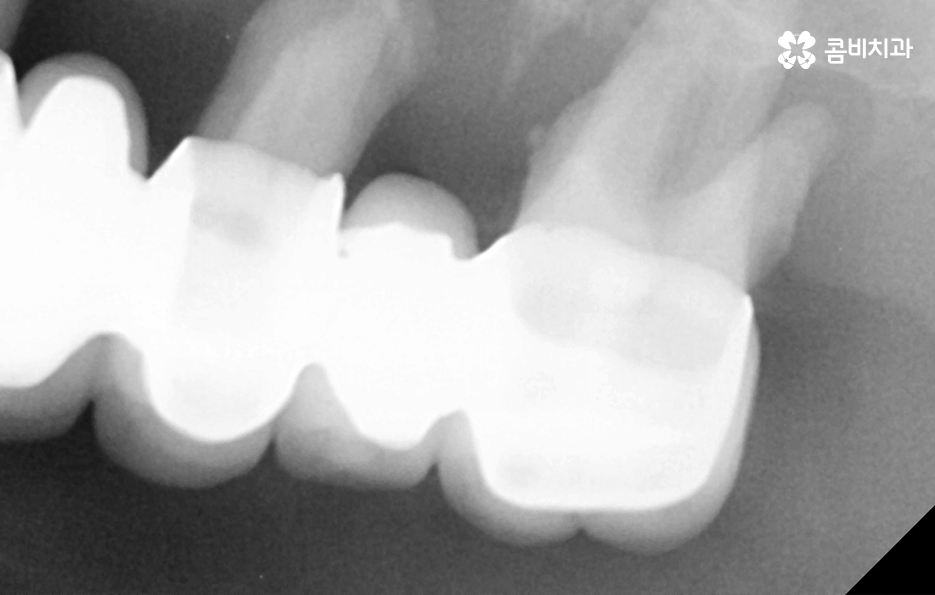

위 환자분의 케이스를 살펴보면 임플란트 시술 후 임플란트 주위염이 발생되어 이미 치조골이 상당히 녹았을 정도로 엑스레이 상에서도 관찰할 수 있어요

임플란트는 보편적으로 분리형이 주로 사용되고 있는데 임플란트의 인공치근은 잇몸 뼈와 골유착이 되어 단단하게 고정이 되어 있고 그 위에 지대주와 보철물이 연결되어 있는 형태이기 때문에 임플란투 수명에 있어서 임플란트의 인공치근 부분이 염증으로 인해 잇몸 뼈가 녹게 되면 임플란트 자체도 흔들리게 되고 결국 제거 후 재수술을 해야 될 수 있어요

흔히 임플란트 시술을 잘하면 약 10년이나 15년 이상도 사용할 수 있을거라 예상하는 분들이 많은데 실제로 15년 이상도 잘 사용하시는 분들도 많지만 사후관리가 잘 안되면 수년만에 임플란트 주위염과 같은 부작용이 발생될 수도 있다는 점에서 지속적인 사후관리가 중요한 시술이라고 생각하시면 좋을 거예요